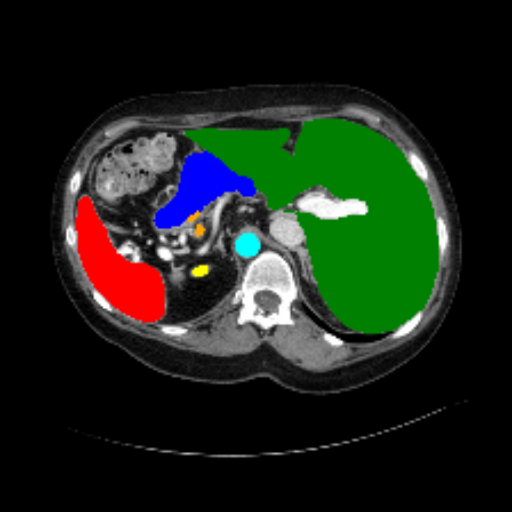

Figure 3 presents a qualitative comparison of segmentation performance on examples from the Synapse, BTCV, ACDC, and ISIC17 datasets. The first two examples (from Synapse) highlight variations in segmentation performance among U-Net, TransUnet, Mamba-Unet, and Swin-Unet. While Swin-Unet performs well in the first example, its performance decreases in the second example, particularly in segmenting the organ highlighted in blue. Additionally, it misclassifies background regions as the class highlighted in orange. In contrast, our approach demonstrates high robustness in segmenting all classes accurately and aligning well with the ground truth masks.

Across BTCV, ACDC, and ISIC17, the comparison methods exhibit varying performance depending on the task and class. For instance, Mamba-Unet struggles to segment multiple organs in BTCV, even misclassifying certain classes as others. In the ACDC dataset, both TransUnet and Mamba-Unet perform poorly in segmenting the three classes. In the last column (ISIC17), Swin-Unet oversegments the skin lesion compared to the ground truth. Unlike the comparison models, our approach consistently delivers effective segmentation across different tasks and datasets.

Slice GT Unet TransUnet Mamba-Unet Swin-UMamba MambaCAFU-V1

Figure 3: Visual comparison of segmentation examples from Synapse (first two examples), BTCV (3-4 examples), ACDC (5th example) and ISIC17 (last example). Columns: input slice, ground truth, Unet, TransUnet, Mamba-Unet, Swin-UMamba, and MambaCAFU-V1.